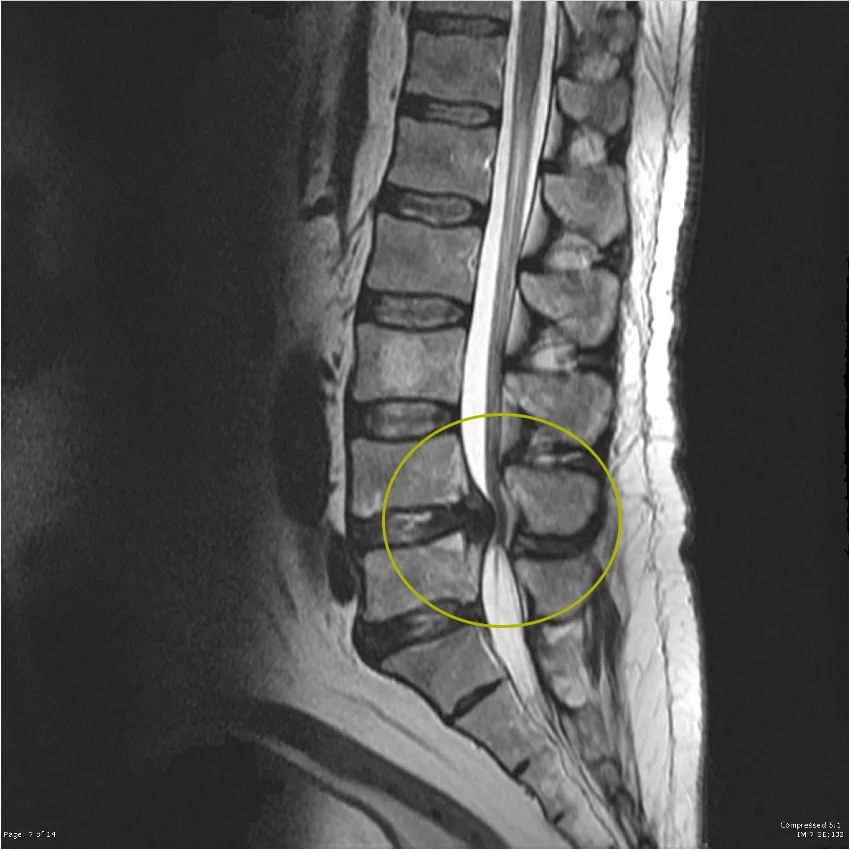

- Magnetic resonance imaging (MRI) is the gold standard for diagnosis, as it provides detailed visualization of neural compression.

Imaging plays a central role in confirming spinal canal stenosis, as it provides a direct visualization of anatomical narrowing and the degree of neural structure compression.

MRI (Magnetic Resonance Imaging) – gold standard

- provides detailed visualization of soft tissues, including intervertebral discs, ligaments, and neural structures

- clearly demonstrates central canal stenosis, spinal cord compression, or nerve root compression

- allows differentiation between central canal stenosis and foraminal stenosis

- non-invasive and does not involve ionizing radiation

In everyday clinical practice, MRI is the most important diagnostic tool for evaluating spinal stenosis, as it provides the most comprehensive assessment of both the cause and extent of narrowing of the spine. It is also essential for treatment planning, particularly when surgical intervention is being considered.